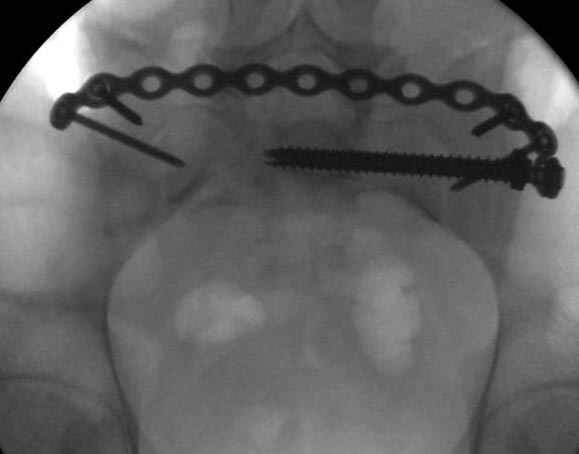

Выбор метода фиксации переломов симфиза зависит не только от опыта врача и традиций, установленных в о тделении, но и от характера повреждения. Например, к изолированным повреждениям симфиза у рожениц подходы другие, нежели к повреждениям симфиза с разрывом тазового кольца в результате высокоэнергетической травмы.

Насчет проволочной (серкляжной) фиксации из-за отсутствия опыта ничего не могу добавить, но неоднократно наблюдал несостоятельность не только после проволочной фиксации, но и после фиксации пластинами, иногда трудно представить взаимодействия тазовых сил.

Здесь слайды случая больного с политравмой, включающей сегментарный перелом бедра и повреждение таза с нарушением тазового кольца, разрыв симфиза и перелома крестца зон 2 и 3.

На множественных слайдах важные моменты операции. Хотел бы подчеркнуть, как важно иметь возможности всех необходимых ренгенограмм, включая компютерную томографию и стандартных внутритазовых рентгенограмм (инлет и оутлет).